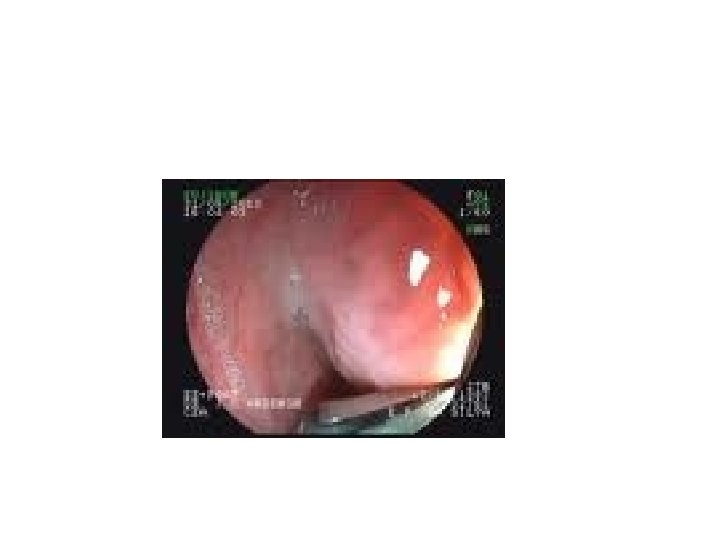

ESÓFAGO: LEIOMIOMA • LEIOMIOMA: ANATOMÍA PATOLÓGICA – Tumor benigno más frecuente del esófago – Macroscópico: blanco, elástico, bien delimitado – Estudio microscópico: • Tumor benigno constituido por células musculares lisas • Se disponen en haces musculares arremolinadas • Bien delimitadas • Epitelio esofágico que la recubre es normal

leiomioma